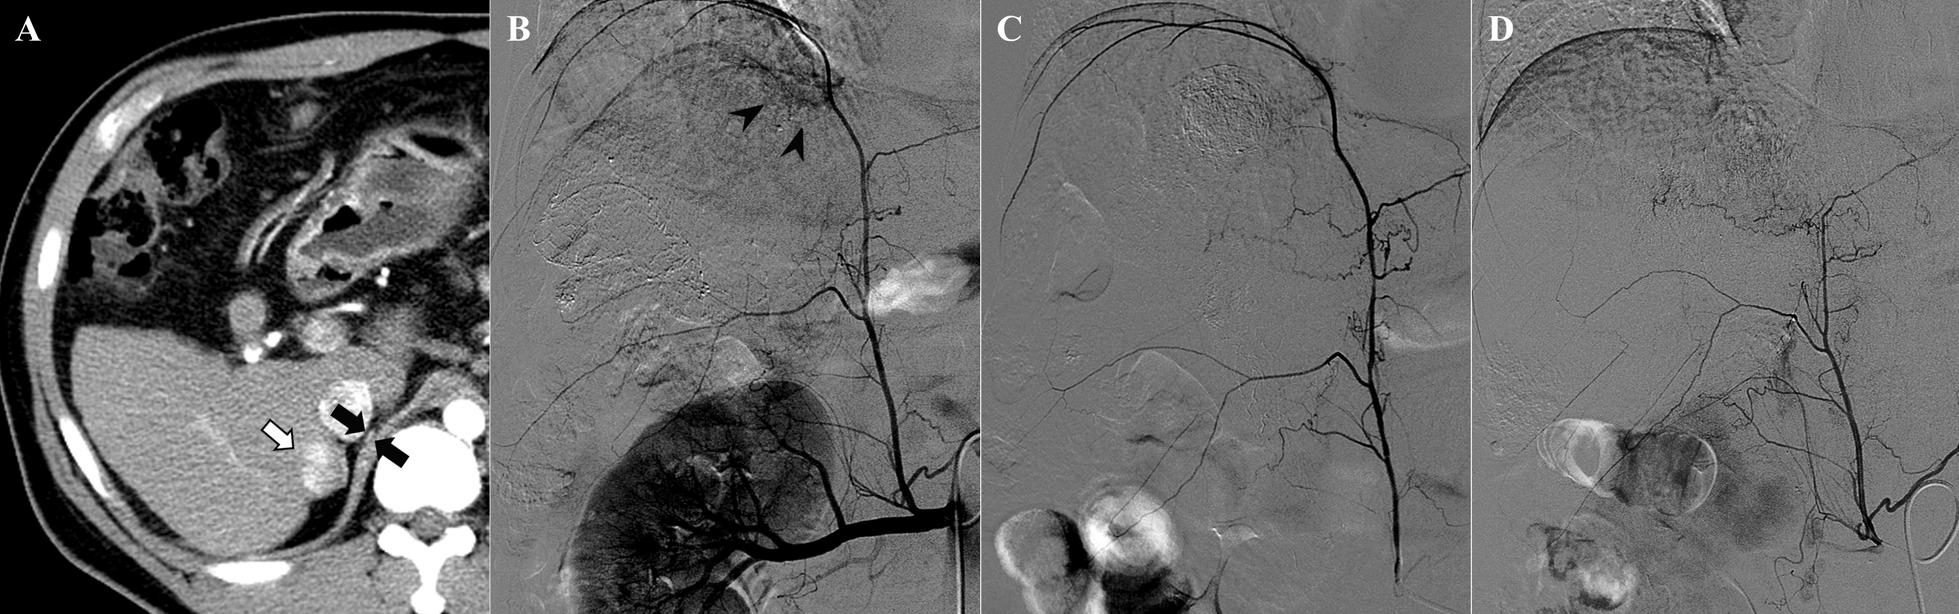

Transcatheter arterial chemoembolization (TACE) via the inferior phrenic artery has been recognized to have its own therapeutic role without causing serious procedural complications. We report a case of diaphragmatic perforation after repeated TACE sessions conducted via the right inferior phrenic artery.

A 43-year-old man diagnosed with hepatocellular carcinoma was admitted to the hospital with a chief complaint of cough. The patient underwent TACE via the right inferior phrenic artery 3 months prior and was discharged without specific complications. Physical examination revealed decreased breathing sounds in the right lower lung zone. Chest radiograph demonstrated a small right pleural effusion. Chest CT scan revealed a small diaphragmatic perforation. The patient was unable to undergo surgical exploration, and a follow-up CT scan after 2 months revealed progression of the right diaphragmatic perforation with massive herniation of omental fat into the thoracic cavity.

经膈下动脉的经导管动脉化疗栓塞(TACE)已被认为具有其自身的治疗作用,而不会引起严重的程序并发症。我们报告了一例因反复经右膈下动脉 TACE 治疗而导致膈穿孔的病例。

一名 43 岁男性被诊断为肝细胞癌,因咳嗽主诉入院。该患者 3 个月前因右膈下动脉接受 TACE 治疗,出院时无特殊并发症。体格检查显示右下肺区呼吸音减弱。胸部 X 线片显示少量右侧胸腔积液。胸部 CT 扫描显示膈小穿孔。患者无法进行手术探查,2 个月后的随访 CT 扫描显示右侧膈穿孔进展,大网膜脂肪大量疝入胸腔。